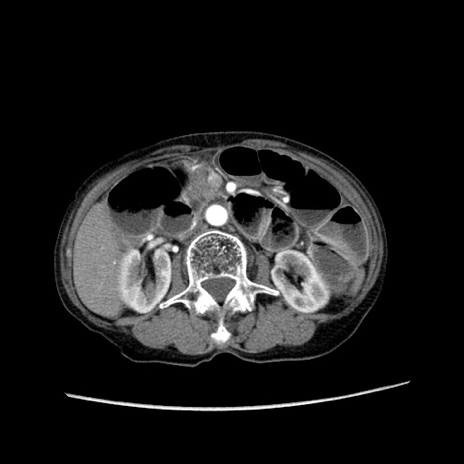

冠状断像

【症例】80歳代女性

【主訴】胸のつかえ感

【現病歴】約9時間前に食後から胸のつかえた感じあり、嘔吐あり、来院。

【既往歴】胃癌(全摘)、胆摘、虫垂炎

【身体所見】心窩部に圧痛あり、反跳痛なし。

【データ】WBC 5700、CRP 0.05